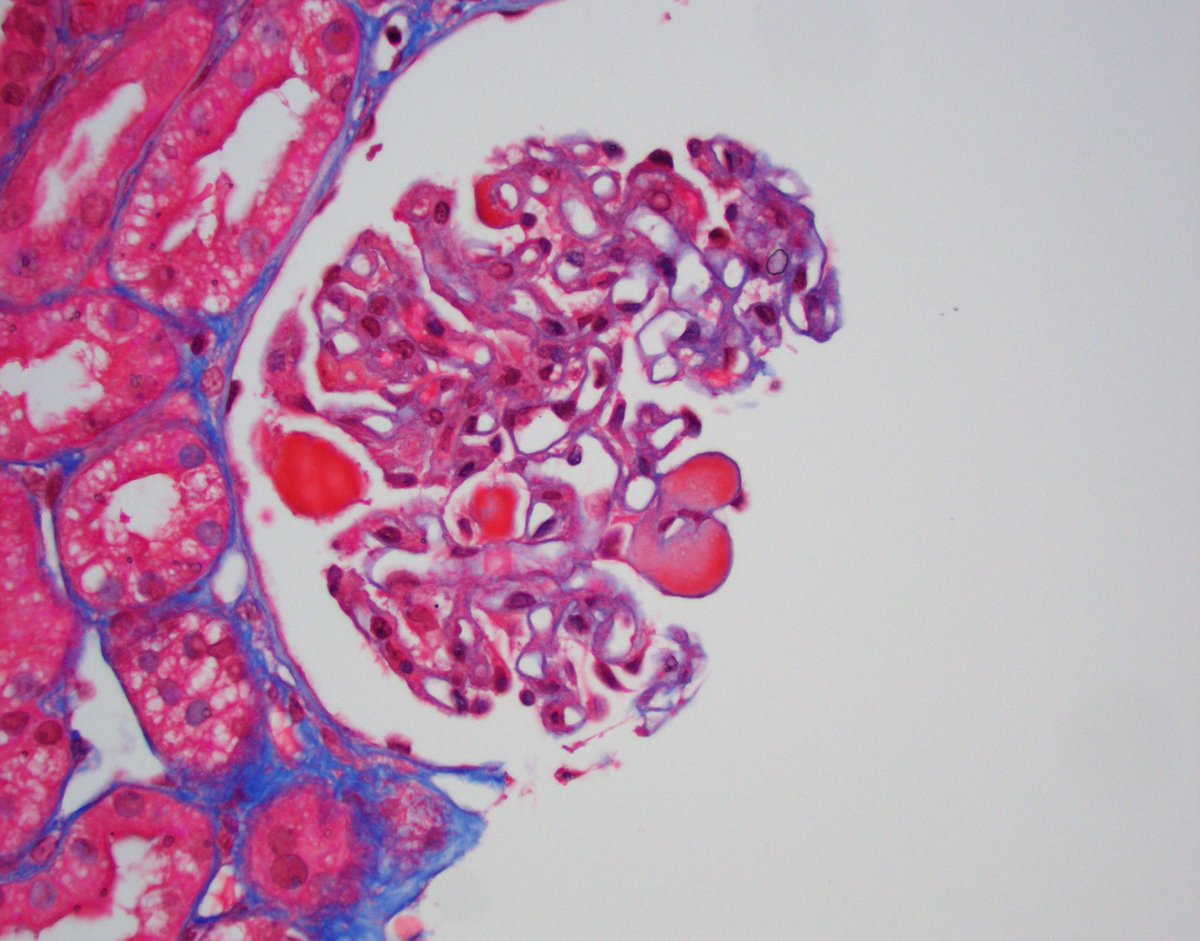

Kidney txp biopsy for AKI (~6 post txp). Tubular injury associated with granular and ropey trichome positive casts. IHC confirmed myoglobin cast nephropathy. CK found to be very high; thought to be due to statin related myopathy. #renalpath #pathwitter #nephrology